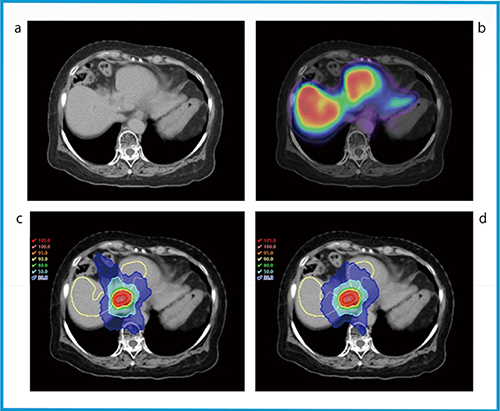

図1 アシアロスペクト画像を用いたinverse planningによる肝機能温存定位放射線治療の例

a:放射線治療計画用CT画像。肝機能の局所的な評価は困難である。

b:放射線治療計画用CT画像とアシアロスペクト画像の融合画像。標的体積周囲の肝機能は過去の治療によって低下している。

c,d:肝機能を温存した放射線治療計画。FLS(ー)に線量制約をかけることにより(c),FLSに線量制約をかけない場合(d)に比べて肝機能が残存している部分の線量を低下させることができる。